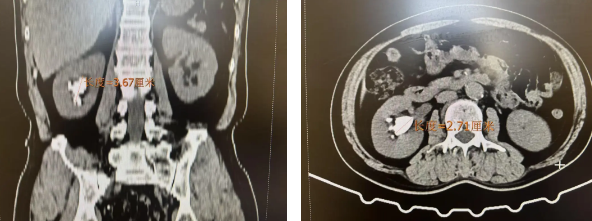

患者王先生(化名)因腰部反复疼痛,经检查发现肾脏鹿角状结石,计划到北京市内三甲医院做经皮肾镜碎石取石术。后经有人介绍,北京燕化医院泌尿外科有专业的碎石团队,可以先去咨询一下,于是王先生来院就诊。经详细检查,发现其肾脏有一4cm大小的鹿角结石。

鹿角形结石因其形状酷似鹿角而得名,这种结石通常体积较大、结构复杂、硬度高,且分支多,填充于肾盂和肾盏内,治疗难度极高。结石长期存在不仅会导致患者腰部疼痛难忍,还严重威胁肾脏功能,若不及时治疗,可能引发肾积水、肾功能衰竭等严重并发症。传统治疗方法往往难以彻底清除,且容易复发,是泌尿外科领域的一大难题。